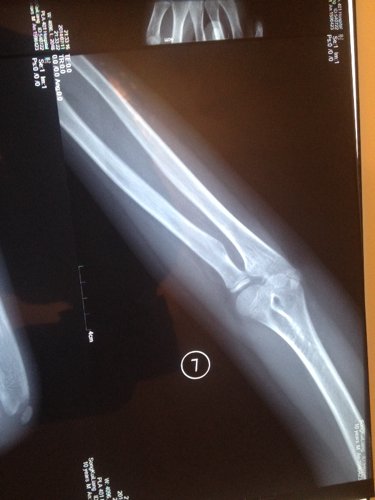

右肘玩的时候摔着了,三个蒙古的医生也没说明白是怎么回事 现在在转胳膊就痛 10岁的小孩 点击展开 匿名用户 2014-07-11 23:14 为您推荐: 其他回答 你好哦,你给宝宝做康复了吗,一般这时候是需要去做一下康复的呢,这样是会更好一些的啊 可靠的悠闲80 2014-07-12 17:41 相关问题 小孩6个多月,抱小孩时胳膊响了一下,孩子就哭个不停,响的那个胳膊就一直不动,请问医生是不是脱臼了 怎么感觉第二张图片上面,那个小孩的胳膊上面怎么好像长了个手指啊,当时检查的时候医生没说什么,今天回 请怎医生我家小孩胳膊上怎么会农了